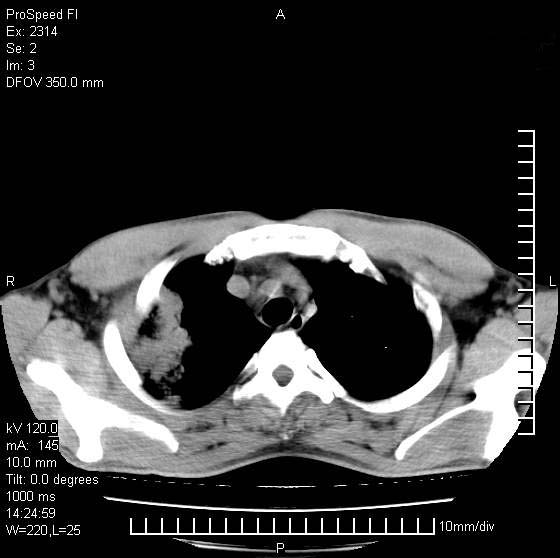

男性,再生障碍性贫血,入院前发热10天,最高40c,右侧胸痛,外院ct示右上,中肺边缘模糊的球性影(就是我现在图中标示的范围),考虑炎症,在我院使用头孢呋辛,洛美沙星10天,高烧消退,自感下午稍有发热,但今天ct示右上,中肺病灶明显扩大,还是考虑炎症,看其中的球型影是否霉菌感染??,是否能排除结核?

肺脓肿,伴双肺播散

支持右肺上叶、中叶外侧段节段性肺炎伴脓肿形成。